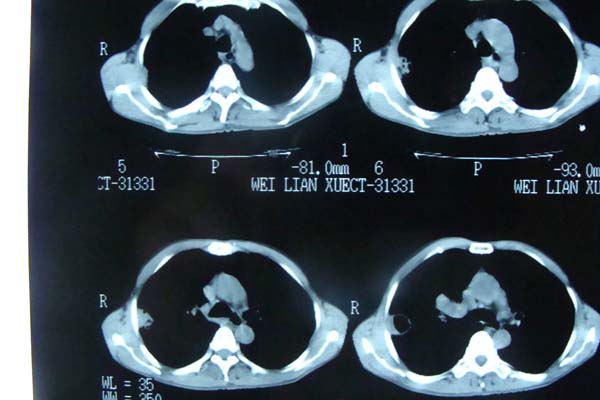

以下是引用pujunzhi在2009-6-21 21:48:00的发言:[br]右肺上叶后段见一空洞性病灶,灶周有渗出即晕征,右肺门肿大---可考虑感染性空洞和癌性空洞,先抗炎抗痨后复查并完善相关检查。有癌性空洞伴肺门淋巴结转移的可能。